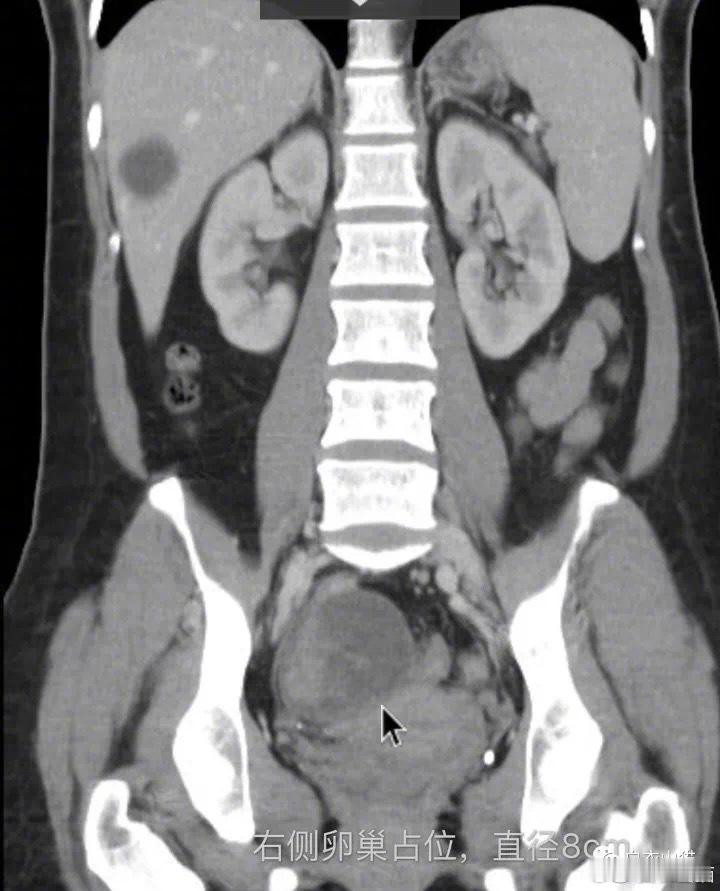

我们知道,卵巢癌术前要做腹部及盆腔CT, 通过CT的表现,做术前分期。

CT发现患者的卵巢肿瘤內有实质性肿块,高度怀疑卵巢癌,但是肿块局限于卵巢內,局部没有淋巴结肿大,也没有发现其他地方有转移灶。

图片4:患者右侧卵巢占位。

在发现患者的右侧卵巢癌的同时,张教授也发现了另外的问题。

图片5:患者右髂外静脉和下腔静脉有血栓形成。

张教授还发现了她右髂外静脉和下腔静脉有血栓形成。